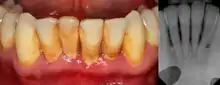

Periodontitis

The defining feature of periodontitis is connective tissue attachment loss which may manifest as deepening of periodontal pockets, gingival recession, or both. This loss of support for the teeth is essentially irreversible damage. Chronic periodontitis is generally slow to moderate in terms of disease progression, although short bursts of increased tissue destruction may occur. Ultimately, tooth loss may occur if the condition is not halted. It is termed localized when less than 30% of sites around teeth are involved, and generalised when more than 30% are involved. clinical attachment loss can be used to determine the severity of the condition, where 1–2mm is slight, 3–4mm is moderate and more than 5mm is severe.[5]